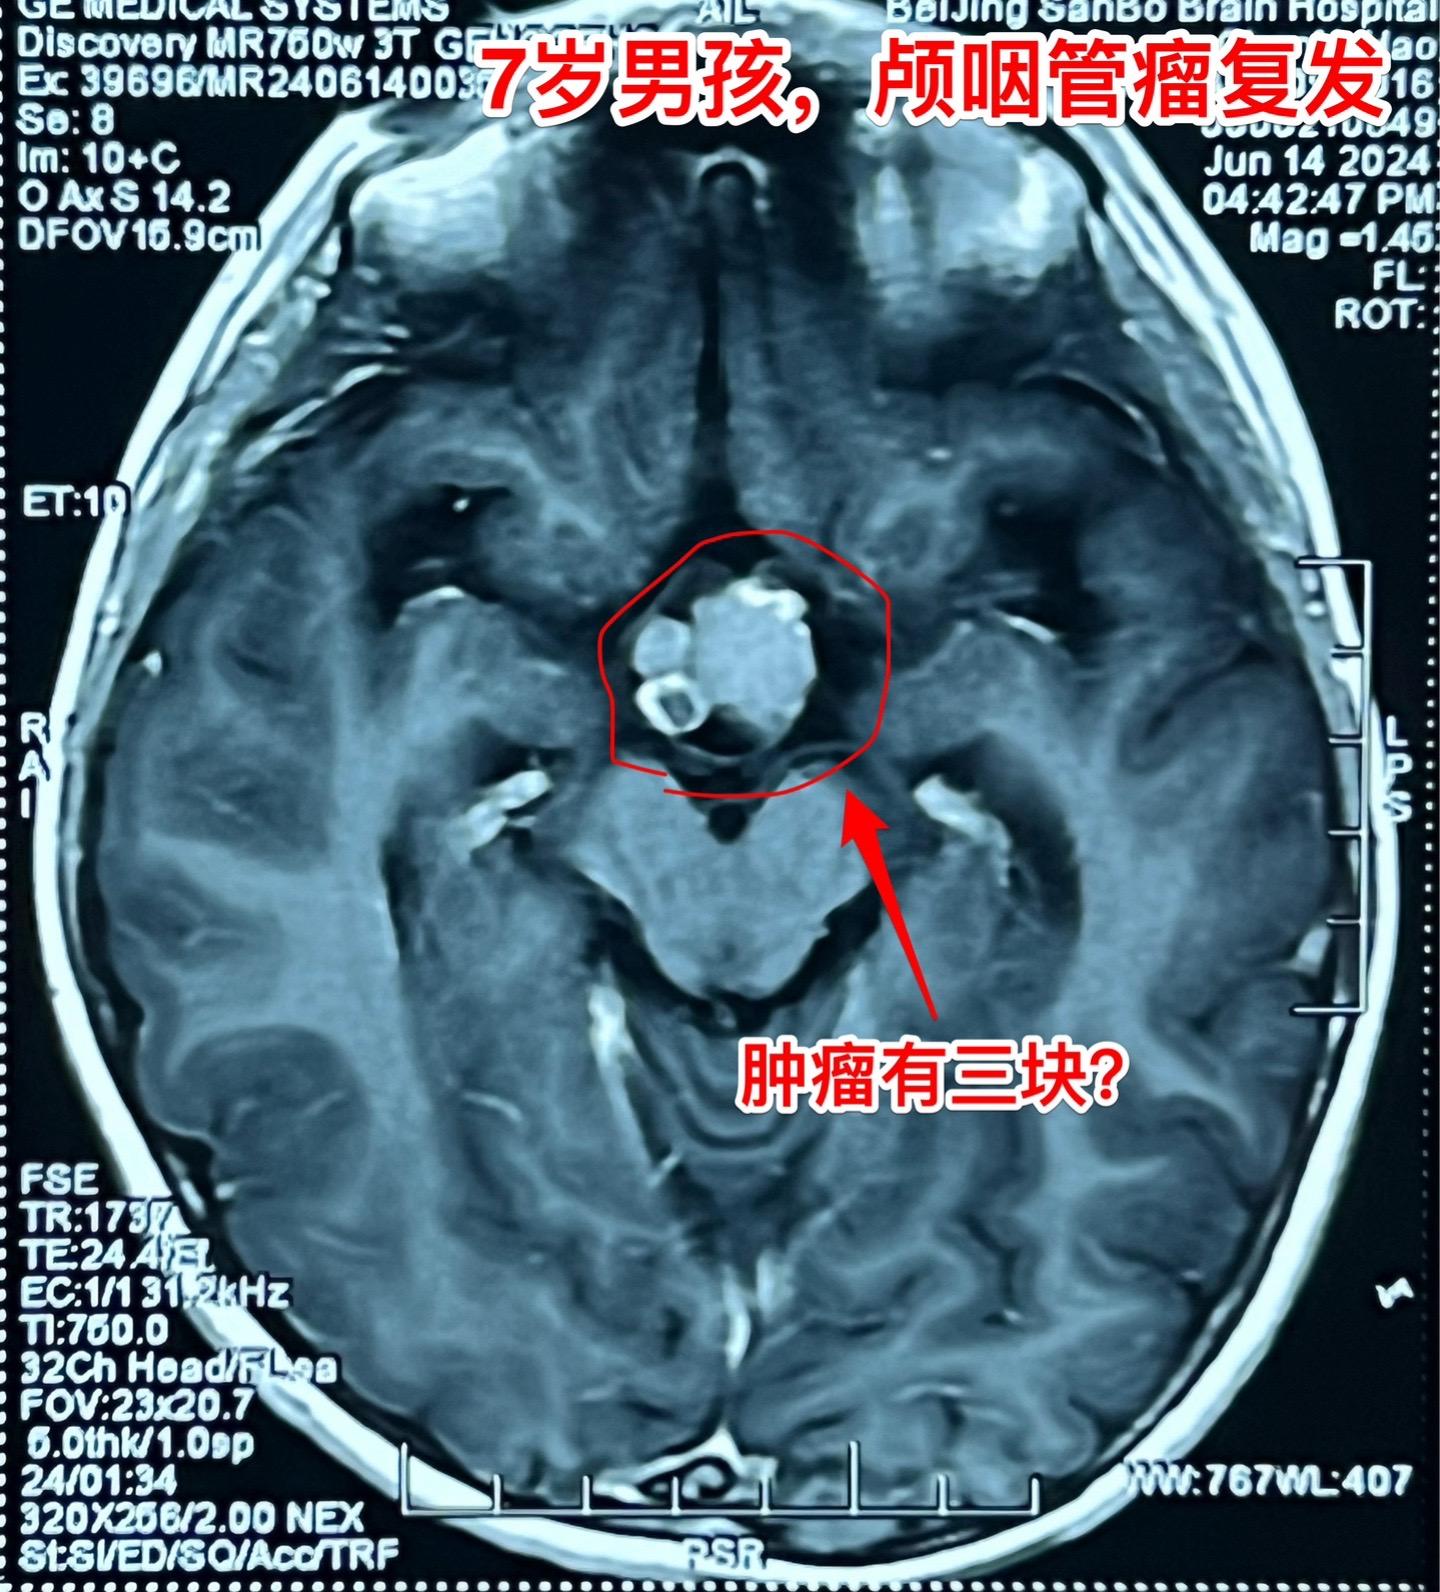

百日咳导致患儿颅咽管瘤手术推迟了三个月。7岁 男孩子三个月前因颅咽管瘤复发,住院准备作颅咽管瘤切除手术。 谁知意外事件不期而遇。 患儿咳嗽不止,只好出院到儿童医院治疗,经检测,咳嗽的原因是百日咳,经过治疗,咳嗽的问题彻底治愈了,过了三个月再次回到三博脑科医院。 2024年6月11日作了开颅手术。颅咽管瘤体积虽然不算大,其实不是一个肿瘤,而是四个肿瘤挨在一起了。 肿瘤当然是完全切除了。好事多磨!颅咽管瘤百日咳